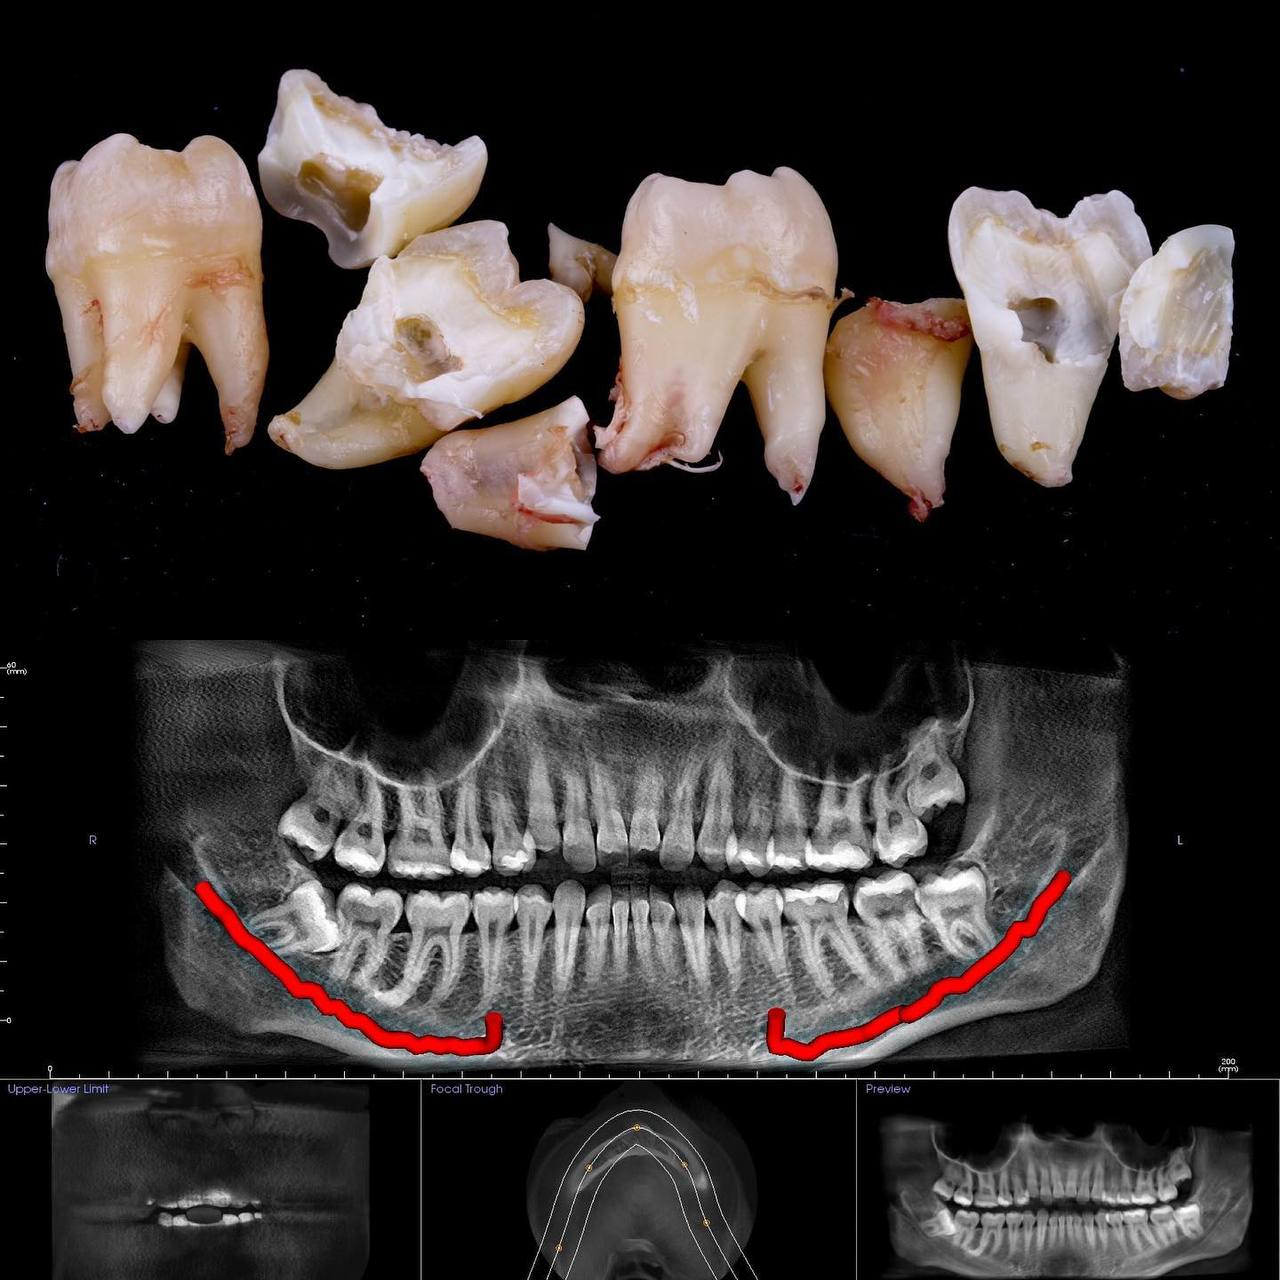

• Разрез десен, освобождение зуба от близлежащей кости ультразвуком и удаление по схеме 1 или 2 - если зуб не прорезался, но беспокоит.

Вырвать зуб мудрости во Львове можно проще, чем тебе кажется, в Космической стоматологии Драганчука. Начни этот путь с простого шага - первичной встречи с хирургом-стоматологом. На консультации мы сделаем основное - направим тебя на 3D компьютерную томографию, чтобы учесть близость нижнечелюстного нерва (нижние 8-ки) и верхнечелюстной пазухи (верхние 8-ки) и составим план удаления зубов.

Вырвать зуб мудрости во Львове можно проще, чем тебе кажется, в космической стоматологии Драганчука. Начни этот путь с простого шага – первичной встречи с хирургом-стоматологом. На консультации мы сделаем основное – направляем тебя на 3D компьютерную томографию, чтобы учесть близость нижнечелюстного нерва (нижние 8-ки) и верхнечелюстной пазухи (верхние 8-ки) и составим план удаления зубов.